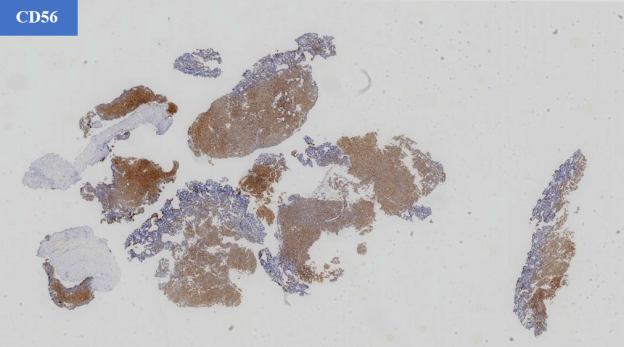

- 神经内分泌标记物:CgA (+), SYN (+), CD56 (+)

- 神经内分泌标记: 肿瘤细胞通常强阳性表达 Syn、CgA、CD56 等。